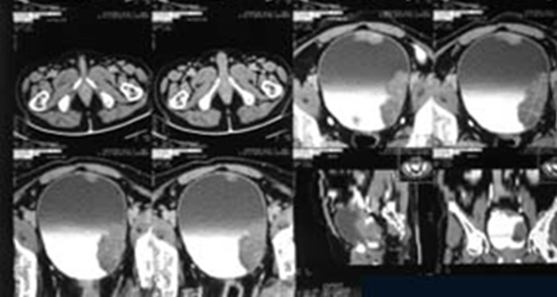

- CT Urography – will detect the presence, depth and type of bladder cancer with functioning of urinary system.

If Transitional Cell Carcinoma – of the Bladder is detected on Biopsy, subsequent evaluation will be done for staging, grading and distant spread of bladder cancer

- Radical Cystectomy (surgery to remove the bladder) – means complete removal of bladder. Many people with stage II or III bladder cancer may need to have their bladder removed.